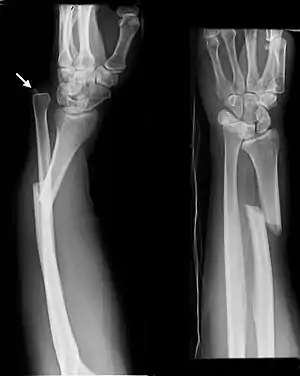

| Midshaft fracture of the radius and ulna | |

Front view of displaced fractured radius and ulna at wrist

Side view of displaced fractured radius and ulna at wrist